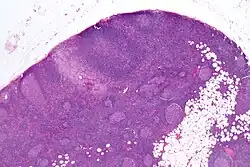

| Micrograph of a lymph node biopsy showing progressive transformation of germinal centres. H&E stain. | |

Microscopic appearance

PTGCs is characterized by:[1]

- follicular hyperplasia (many follicles),

- focally large germinal centres, with poorly demarcated germinal centre (GC)/mantle zone interfaces (as GCs infiltrated by mantle zone lymphocytes), and

- an expanded mantle zone.